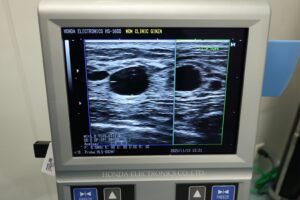

※他院で施術を受けてしこりができた患者様のエコーのお写真

上記のエコー写真を見ると、バスト内に黒い影(しこり)が映り込み、周囲の組織を圧迫している様子が確認できます。過去に注入した脂肪注入が定着できず、部分的にしこりとなって残っている状態です。

一箇所への集中的な注入により、脂肪細胞の中心部まで血流が行き渡らず壊死したことが主な原因です。放置すると周囲組織にカルシウムが沈着して硬化が進み、硬さや変形が目立つケースもあります。